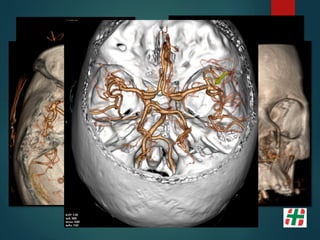

Malformaciones Vasculares

 Las MAV son aglomeraciones anormales focales de arterias y

venas dilatadas en el parénquima cerebral.

 Pérdida de organización vascular a nivel subarteriolar y la

falta de un lecho capilar resulta en un shunt arteriovenoso.

 El nido, está conectado por una o varias fístulas.

Friedlander, et al. N Engl J Med 2007;356:2704-12.